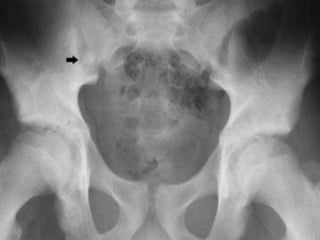

2. ANEURISMA DE AORTA ABDOMINAL

5. Aneurisma disecante de aorta abdominal